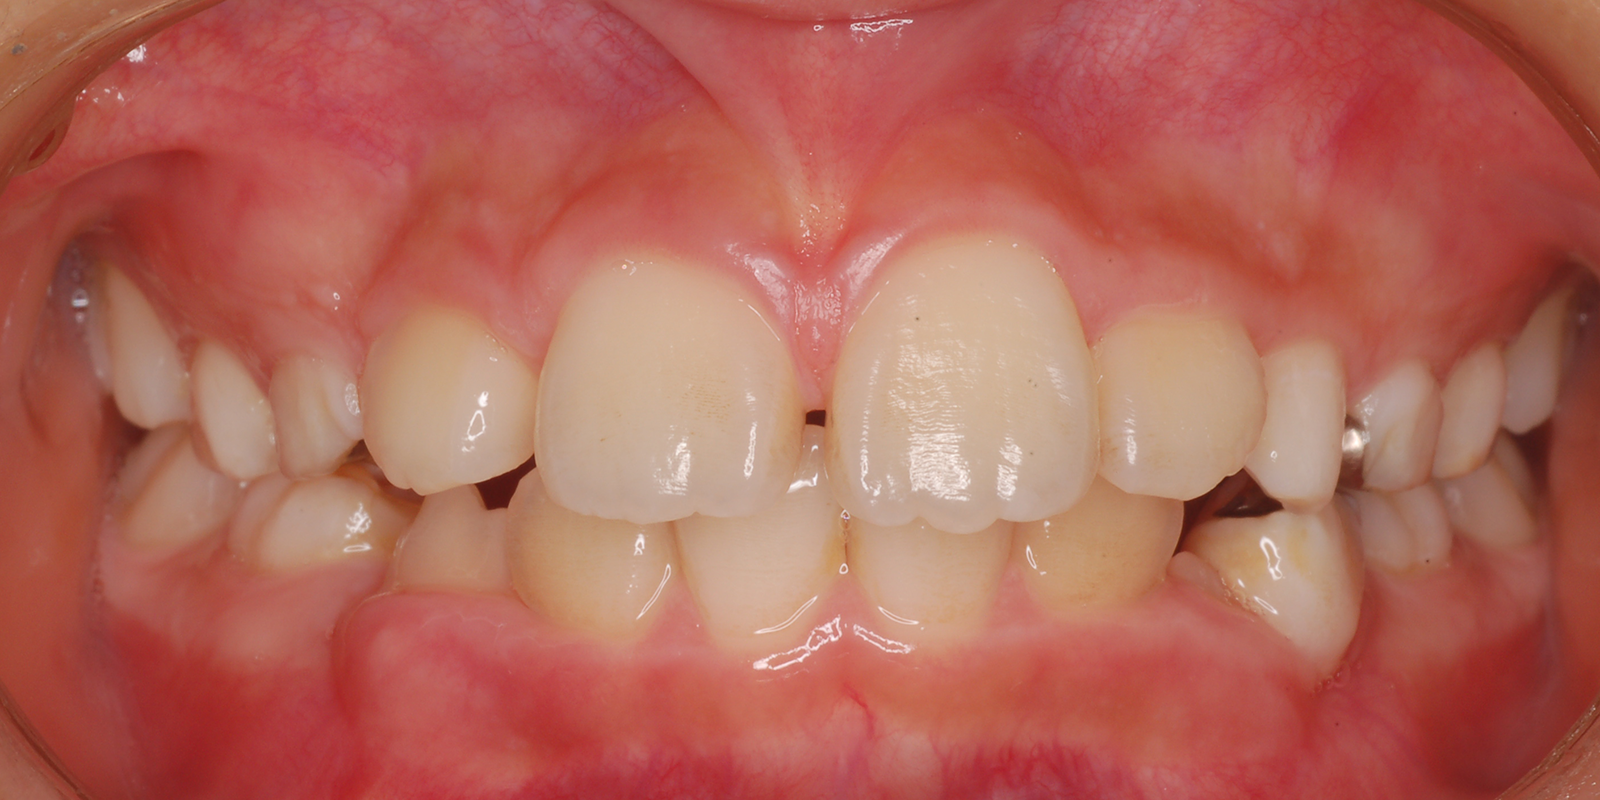

叢生・ガタガタの歯並びの治療

術前

術中

術後

術前・術後の比較

| 主訴 | 叢生 |

| 診断 | アングルⅡ級1類 |

| 初診時年齢 | 9歳10か月 |

| 装置 | ヘッドギアー(1期治療) 若干上顎が大きく、大臼歯関係が上顎大臼歯が前に出て上顎前突のため、上顎大臼歯を遠心に送るためヘッドギアーを使用しました。 |

| 抜歯・非抜歯 | 上下左右第1小臼歯を抜歯、マルチブラケット(2期治療) 大臼歯関係が正しい関係になりましたが、叢生、歯軸の関係が悪いので、永久歯の抜歯を行いました。 |

| 治療期間 | 1期治療:1年10ヶ月 2期治療:3年 |

| 通院回数 | 1期治療:13回 2期治療:約36回 |

| 治療費 | 約100万円 矯正歯科治療は公的医療保険の適用外の自費(自由)診療となります |

| 治療のリスク | ・装置を使用しなければ効果が出ない ・歯に痛みが出ることがある ・取り外しのため、なくすことがある ・ブラッシングが悪い場合虫歯や歯肉炎になります |